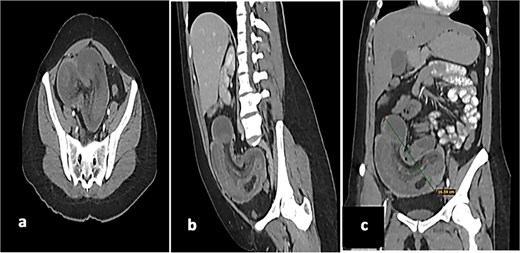

Vital signs on admission were stable: heart rate 82 beats per minute, blood pressure 115/62 mmHg, respiratory rate 19, temperature 36.7°C, and oxygen saturation 96%. A computed tomography scan showed ileocecal intussusception with a ‘donut’ sign, wall thickening of the cecum, and a 16 cm segment of intussuscepted ileum with pneumatosis in the cecum.

(a) Axial tomography shows the donut sign, thickening of the cecum of up to 10 mm, with reinforcement of the mucosa and muscles, as well as hypodensity of the submucosa. (b) Sagittal tomography showing a loop of ileum and mesentery that are introduced intraluminally into the cecum and ascending colon. (c) Coronal tomography showing a 16 cm long segment of ileum with intussuscepted pneumatosis in the cecum and ascending colon.